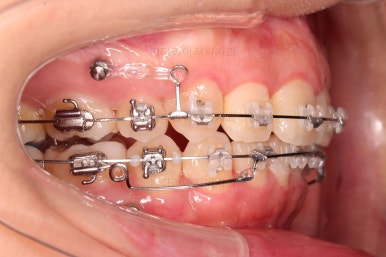

아래 앞니는 깊숙하게 솟구쳐 오른 치아를 밑으로 끌어내리기 위해 미니스크류를 식립하게 됩니다.

아랫니가 매우 밑으로 많이 내려온게 보이시죠?

과개교합은 비교적 초반에 개선이 되었습니다.

아래 앞니의 높이가 개선된 뒤, 아랫니도 가지런하게 해줍니다.

윗니도 어느새 치아를 뽑은 공간이 많이 줄었네요.

아랫니도 발치를 하고요.

윗니는 아랫니가 뒤로 들어가는 만큼 더 뒤로 밀어야 되기 때문에 미니스크류를 이용해서 뒤로 당기기를 해줍니다.